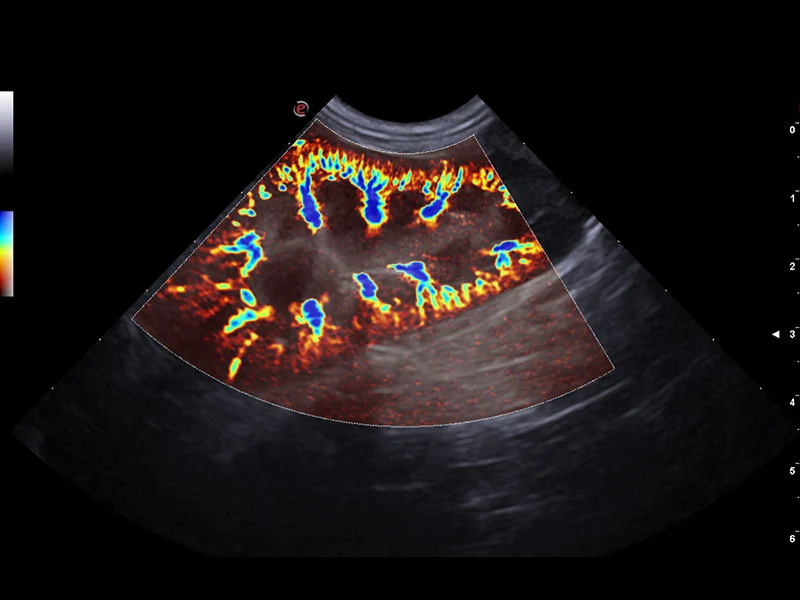

XFlow - za povećanje osetljivosti i rezolucije tokom snimanja krvotoka

microV – brza neinvazivna hemodinamička procena sa visokom osetljivošću za perfuziju tkiva.

KLINIČKE SLIKE